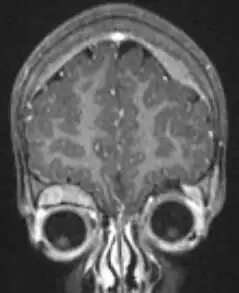

Resonancia magnética de una niña de 2 años con neuroblastoma intracraneal. | ||